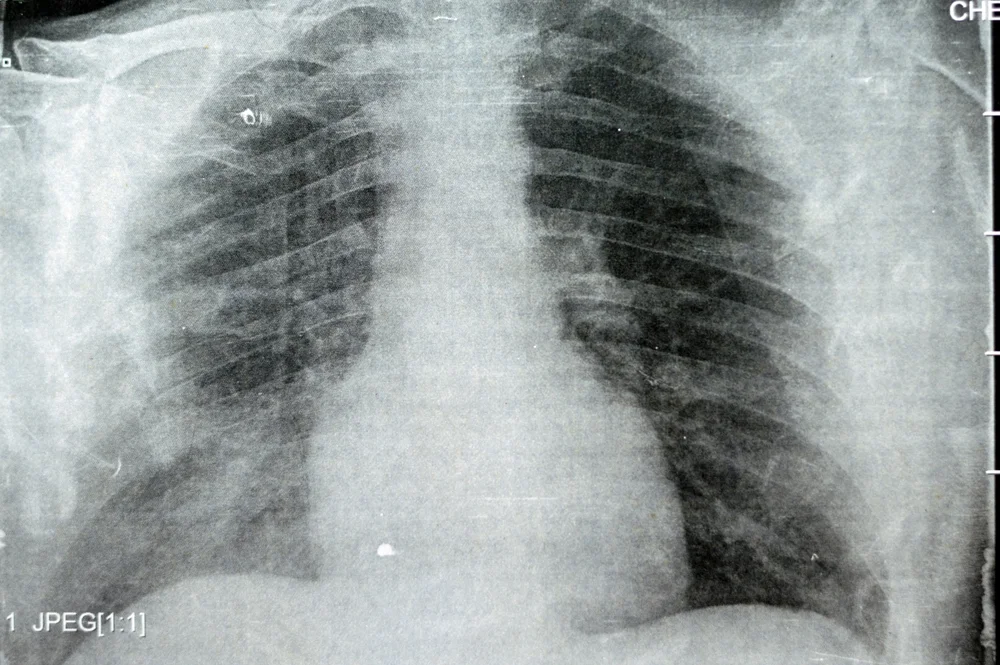

דלקת ריאות היא מצב רפואי שבו הריאות מתנפחות וגורמות לקשיי נשימה, שיעול ותסמינים נוספים. המחלה יכולה להיגרם על ידי חיידקים, וירוסים או גורמים אחרים, והיא נפוצה במיוחד בקרב ילדים וקשישים.

דלקת ריאות ויראלית נגרמת על ידי וירוסים שגורמים למחלות נשימה אחרות, כגון נגיף השפעת (אינפלואנזה), נגיפי קורונה (כולל SARS-CoV-2 שגורם למחלת COVID-19), ונגיף ה-RSV (Respiratory Syncytial Virus). בזיהום ויראלי, הסיכוי להדבקה דומה לסיכוי ההדבקה בנגיף שגרם לדלקת מלכתחילה, שכן רבים מהוירוסים הללו מדבקים מאוד ומתפשטים בקלות באוכלוסייה.